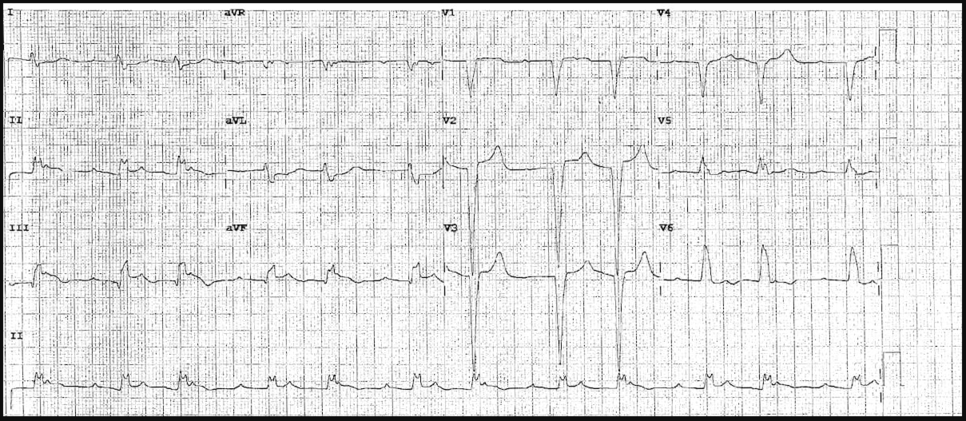

There is 1mm concordant ST elevation in aVL (= 5 points)

There is concordant ST depression in V2-5 (= Sgarbossa positive).